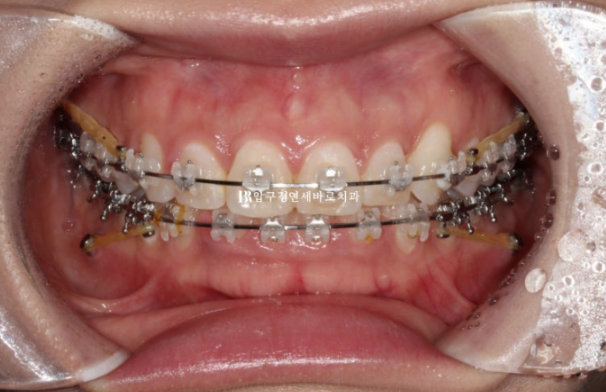

24.03

치료시작 11개월째 모습입니다.

미니스크류를 심고 전체 치열을 사랑니 공간으로 밀어내는 중입니다.